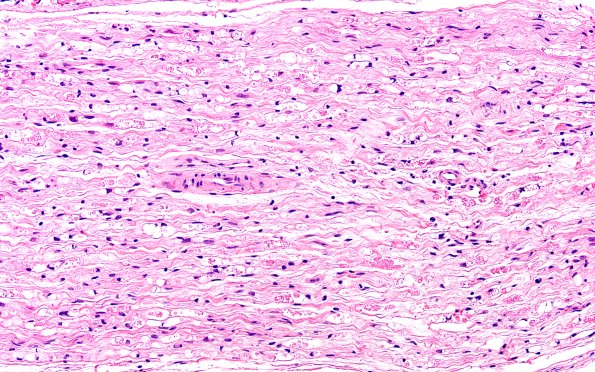

7B3 Ovoids (Case 7) H&E 20X

Numerous degenerating axons are seen in these longitudinal sections. (H&E)